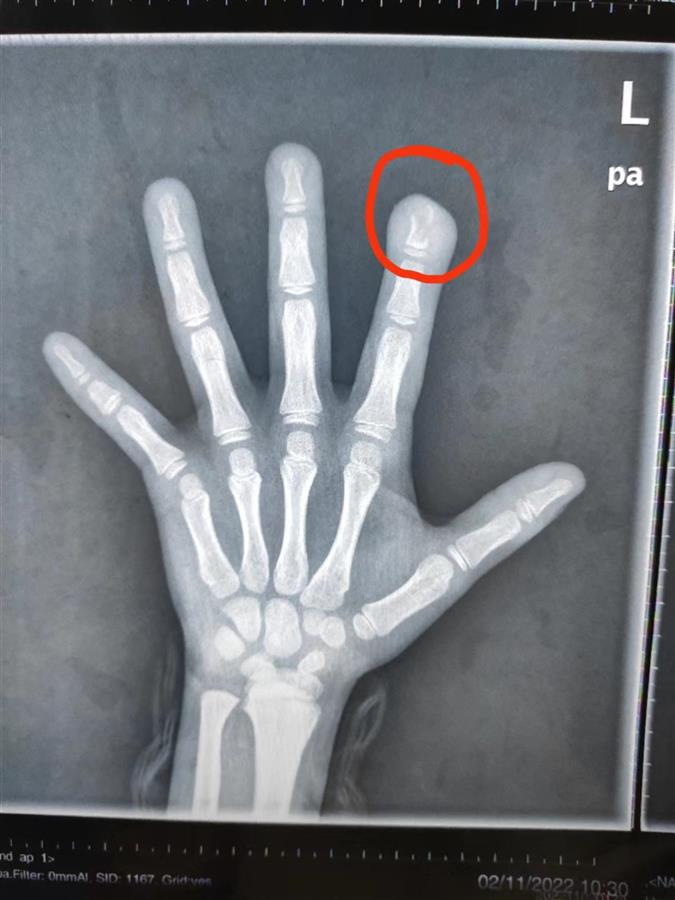

“送来时,孩子左手食指指尖破溃感染,还有脓性分泌物流出。”该院小儿骨科副主任医师徐剑说,文文食指指骨远节有骨质破坏,近1厘米长,是细菌侵蚀导致的,也是常说的骨髓炎。原来,文文从4岁起就有咬指甲的习惯,十个指头的指甲都被她咬得坑坑洼洼,父母怎么劝说她都不听。上月,文文咬破了左手食指指尖,但一直没告诉家人,没想到导致严重感染。

文文的食指有部分残缺

针对文文的情况,目前彻底根治的方法就是“刮骨”,也就是将骨内局部感染的病灶彻底刮除。术中,医生看到孩子左手食指指骨如同被虫蛀过一般,将感染的骨头彻底刮掉后,再用抗生素冲洗,最后将人工皮覆盖手指创面。术后,手指功能和外观将慢慢恢复正常。